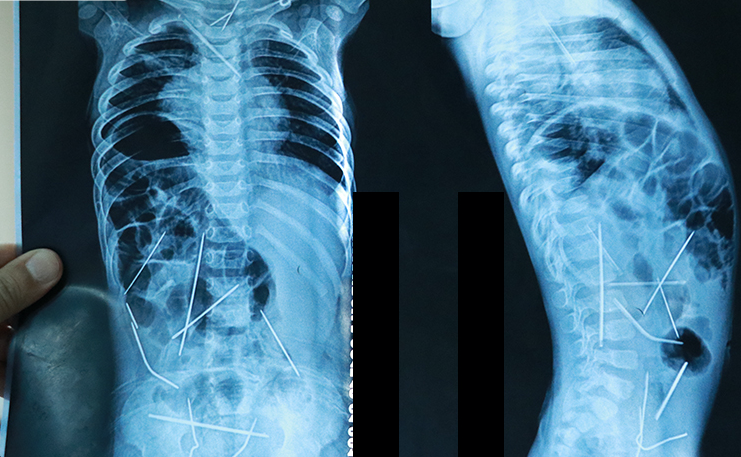

Fərqanə şəhərində sidiyə gedə bilmədiyinə görə xəstəxanaya gətirilən 11 aylıq körpəni rentgen edən həkimlər şoka düşüb.

Medicina.az xəbər verir ki, rentgen çəkimində uşağın orqanizminin müxtəlif yerlərində ilişib qalmış iynələr fiksə olunub. Uşaq təcili əməliyyata alınıb.

9 saat davam edən əməliyyat zamanı orqanizmdən 13 tikiş iynəsi çıxarılıb. Digər çətin yerdə qalan 3 iynə növbəti əməliyyatda çıxarılacaq. Uşağın anası bu iynələrin uşağın bədəninə necə düşdüyünü izah edə bilməyib.

Güman olunur ki, kimsə bilərəkdən iynələri körpənin bədəninə yeridib.